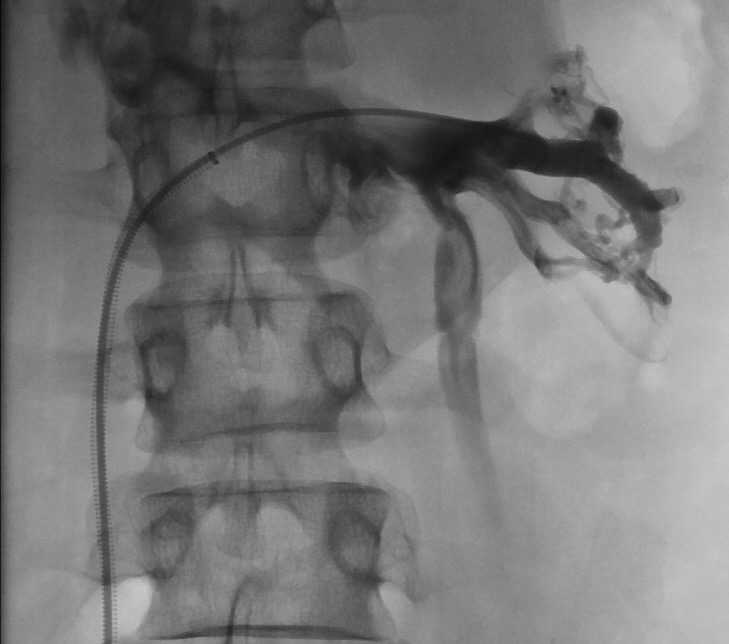

🙌🏻 Webinar JuRI Saison 3-EP 4: ☢ Radiologie Interventionnelle multi-modale : l'endovasculaire au service du percutané !! 👨🏫 Pr J.Garnon @percut/ Dr G.Goyault 🗓 Lundi 26 juin 19h 🧑💻Lien zoom: univ-amu-fr.zoom.us/meeting/regist… @SFRadiologie @cirsesociety @ETF_IRtrainees @aphm_actu